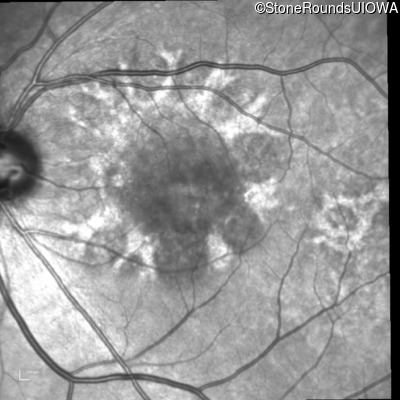

Age at visit: 49 years

This 49 year old man first experienced some mild metamorphopsia at age 35.

Age at visit: 51 years

Age at visit: 52 years